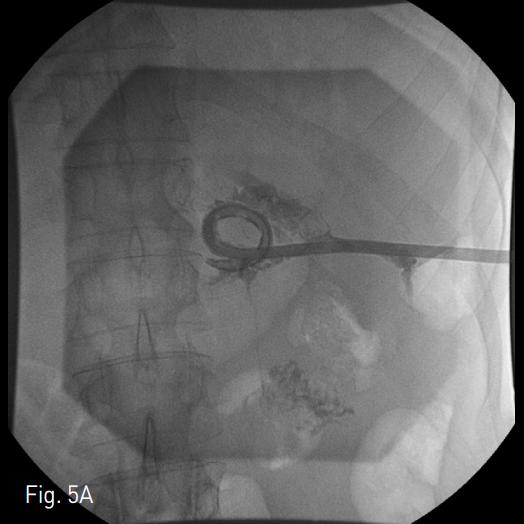

초음파 유도하에 왼쪽 측와위에서 췌장 미부 주위 액체 저류를 조준하여 22 gauge Chiba needle로 천자하였음. 조영제를 주입하여 액체 저류 안에 들어온 것을 확인하고 차례로 확장기를 진입시킨 후 18 Fr Thal-Quick chest tube (Cook, Bloomington, IN,USA)를 거치하였음 (Fig. 2). 이후 냄새가 나는 연갈색의 농이 배액되어, 카테터를 배액용기에 연결한 후 시술을 종료 함. 이후 2개월간 11번 동안 혈관조영실을 방문하여 평균 8000cc정도의 생리 식염수를 이용한 적극적인 세척과 함께 50cc 관장용 주사기로 흡인하여 괴사 제거술을 시행하였음 (Fig. 3). 출혈을 피하기 위해, 괴사 제거술은 흡인으로 쉽게 제거되는 괴사물 정도에 대해서만 국한하여 시행하였으며, 과도한 유도철사의 움직임은 최소화하였음. 흡인물에서 육안으로 신선 혈액이 확인되는 경우는 바로 시술을 종료하였음. 2개월 뒤 추적 전산화 단층촬영술 축상면 영상에서 삽입되어 있는 도관과 함께 주변 괴사 조직과 액체 저류가 양이 매우 감소한 것을 확인하였음 (Fig. 4). 당시에도 거짓동맥류 등의 중요 합병증은 보이지 않았음. 이에 14 Fr MSL catheter (Cook, Bloomington, IN, USA)로 교체하여 배액을 마무리하기로 하였음. 이후 조영제를 주입하였을 때 소장과의 샛길이 보였고 통제된 샛길 (controlled fistula)를 형성하기 위해 1주일간 카테터를 유지하기로 하였음. 1주일 뒤에 환자 이전의 발열 및 복통 증상이 호전되어 다시 악화되지 않음을 확인한 후 유도철사와 5 Fr KMP catheter (Cook, Bloomin gton, IN, USA)를 이용하여 샛길의 경로를 조영제로 확인하고 4mm MicroNester (Cook, Bloomington, IN,USA)와 Histoacryl (B. Braun, Melsungen, Germany),

Lipiodol Ultra Fluride (Guerbet, Roissy, France)의 혼합물을 이용하여 색전술을 시행하였음. 이후 조영제를 주입하였을 때 더 이상 소장으로의 샛길은 보이지 않아 Nelaton catheter를 이전의 삽입경로에 일시적으로 거치한 후 시술을 종료하였음 (Fig. 5).

Fig. 5

Fistula between fluid cavity and jejunum was noted (A). Successful navigation to fistula tract was done with 0.035inch hydrophilic guide wire and 5 Fr KMP catheter (Cook, Bloomington, IN, USA) (B). Controlled fistula tract was embolized with 4mm Tornado (Cook, Blooming ton, IN, USA) and Histoacryl (B. Braun, Melsungen, Germany), Lipiodol Ultra Fluride (Guerbet, Roissy, France) mixture. Post-embolization tubogram showed no demonstation of previous fistula. Nelaton catheter was deployed to formation of con trolled fistula (C). 1 week later, bedside removal of Nelaton catheter was done.